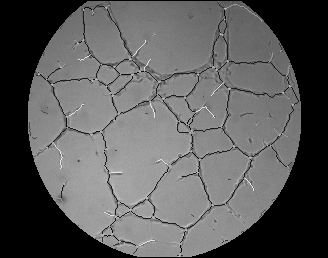

De cada una de las imágenes (ver Fig.3) se pueden extraer una serie de parámetros consensuados como significativos en los procesos angiogénicos. En todas las imágenes se puede observar la presencia de canales (cerrados y abiertos) de diferentes longitudes y con su característica intrínseca de linealidad, células aisladas, grumos de células, fondo de textura uniforme y un halo circundante de mayor brillo que es una interferencia incorporada por condiciones de contorno en la adquisición. El procesamiento individual se puede dividir a su vez en 3 partes: 1) pre-procesamiento, 2) realce de las morfologías de interés, y 3) post-procesamiento.

Figura 3. Imagen original. Figura 4. Detección de halo. Figura 5. Area de trabajo

1) El pre-procesamiento tiene como objetivo la determinación del área de trabajo. Se eligió como área de trabajo, la zona de la imagen inscrita en el halo sobreiluminado circundante. El halo se caracteriza por ser un anillo provocado por la reflexión de la luz en el menisco que origina el líquido sobrante en cada pocillo. Se aplica a la imagen original un filtro de mediana de [15x15] que realza el anillo suavizando a la vez las estructuras interiores (ver Fig.4) de forma que se destaca la frontera interior entre éste y el área de interés. Tomando los perfiles de la imagen que siguen las dos diagonales entre vértices, se determina mediante las respectivas derivadas de primer grado, y tomando como apoyo el histograma de grises, los cuatro límites fronterizos puntuales. Se calculan los centros y radios de las cuatro posibles circunferencias que pasan por estos puntos, y si se cumplen las condiciones de proximidad/agrupación adecuadas, se elige como circunferencia delimitadora del área de trabajo la que tiene por centro el promedio de los cuatro y radio el mínimo de las cuatro. En el caso de que no se den dichas condiciones de proximidad, se fija el área de trabajo como la intersección de las cuatro circunferencias determinadas. En cualquier caso y como final del pre-procesamiento, queda determinado el área de trabajo (ver Fig.5) mediante una matriz de índices que funciona como máscara.

2) El siguiente paso es el realce de las interconexiones celulares o canales. Para destacar los canales se adopta una estrategia indirecta, ya que no se aborda el problema identificando directamente los canales, sino que se discrimina el fondo de las imágenes que tiene una textura uniforme y regular en comparación con los canales. Para diferenciar el fondo del resto de la imagen, se realzan los bordes de la imagen en magnitud (ver Fig.6) y fase (ver Fig.7) mediante derivadas perpendiculares (método de Sobel). Tomando agrupaciones relativamente grandes de puntos [15x15], se efectúa un análisis no lineal de la imagen, determinando la media y varianza de la magnitud absoluta de los bordes. Se obtiene de esta forma una sencilla referencia estadística diferenciadora del fondo y los canales. Para mejorar la diferenciación es necesario incluir un criterio de fase teniendo en cuenta la linealidad de los canales; se procesa la imagen de fases, indicadora de la dirección de los bordes, de forma que se destacan las zonas que mantienen un determinado criterio de linealidad. Como resultado se obtiene una imagen binaria (ver Fig.8) en la que quedan marcadas las zonas alineadas con apertura inferior a 20º.

Figura 6. Detección bordes: magnitud Figura 7. Detección bordes:

fase Figura 8. Umbral de

linearidad

A partir de la media/varianza de referencia obtenida anteriormente en la matriz de amplitudes absolutas de bordes y de la imagen obtenida del criterio de linealidad, la discriminación del fondo se realiza aplicando este triple criterio a cada píxel del área de trabajo: umbral de media, umbral de varianza y linealidad, de forma que un píxel pertenece al fondo si en su vecindario de [3x3] sólo cumple uno de ellos o ninguno. El resultado de la aplicación de este criterio de forma directa es el que se puede ver en la figura 9, que posteriormente se somete a un filtrado no lineal de forma que se eliminan los píxeles aislados siendo el resultado final el mostrado en la figura 10.

Figura 9. Discriminación del fondo Figura 10. Filtrado para limpieza fondo

El siguiente procedimiento es aplicar un proceso de binarización (ver Fig.11), seguido de otro de esqueletonización (ver Fig.12), de forma que quedan perfectamente delineados los canales detectados. En la figura 13 se puede observar la superposición de la imagen resultantes del pre-procesamiento (paso 1) y del procesamiento (paso 2); se marcan en negro los canales conectados y en blanco los canales aislados (no conectados).

Figura 11. Binarización Figura 12. Esqueletonización

Figura 13. Superposición de imagen con trazado de canales detectados.